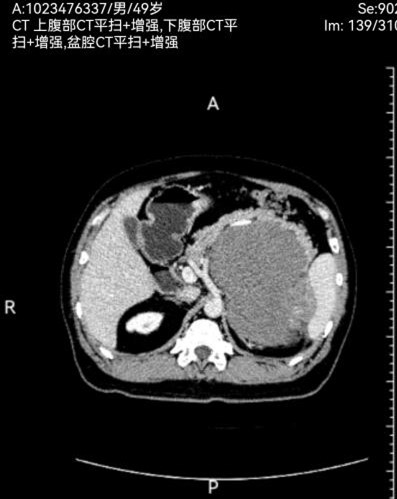

此次两名患者均因“腹部胀痛、包块及进食受限”入院,经增强CT三维重建及磁共振等检查,确诊为腹膜后巨大肿瘤。一例左侧腹膜后肿瘤,长径达30cm,重约4.8kg,紧贴腹主动脉及腹腔干,侵犯脾动脉根部及胰体尾、脾门、右肾及右肾上腺,与结肠系膜粘连紧密,挤压胃肠道引发不全梗阻;另一例右侧腹膜后肿瘤,长径40cm,重约3.2kg,侵犯结肠系膜根部血管,血供丰富,同时挤压肝门及十二指肠,存在右肾蒂损伤风险。